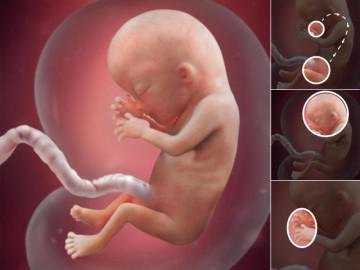

Thai nhi 12 tuần tuổi phát triển ra sao?

Sự phát triển mang tính bước ngoặt lớn nhất trong tuần này của bé là: phản xạ. Các ngón tay của bé đã có phản xạ đóng – mở rõ ràng, các ngón chân thì cong lại. Thai nhi sẽ cử động nếu bụng mẹ bị kích thích, mặc dù bạn hoàn toàn chưa cảm thấy gì.

Từ đầu đến chân, tuần này, bé yêu của bạn dài khoảng hơn 5,4 cm

Ruột của bé, vốn trước thời điểm này đã phát triển nhanh và nhô vào dây rốn, sẽ bắt đầu di chuyển vào trong khoang ổ bụng, thận cũng thực hiện nhiệm vụ bài tiết nước tiểu vào bàng quang của bé.

Trong khi đó, các tế bào thần kinh cũng tăng lên theo cấp số nhân, và các khớp nối thần kinh cũng đang hình thành mạnh mẽ trong não của bé. Khuôn mặt bé dần rõ nét: mắt đã bắt đầu dịch chuyển lại gần nhau ở phía trước thay vì nằm cách xa nhau, tai đã mọc đúng vị trí…

Từ đầu đến chân, tuần này, thai nhi dài khoảng hơn 5,4 cm (có kích cỡ gần giống quả chanh xanh), nặng khoảng 14g.